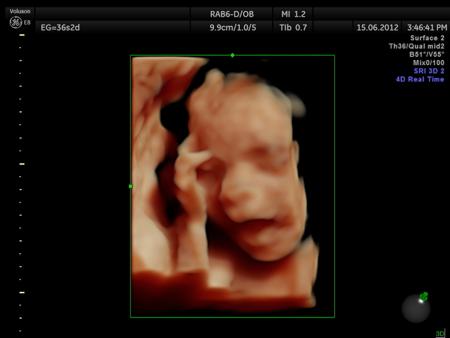

Fotografías de ecografías 4D HD/5D

Haga click sobre las imágenes para ampliar